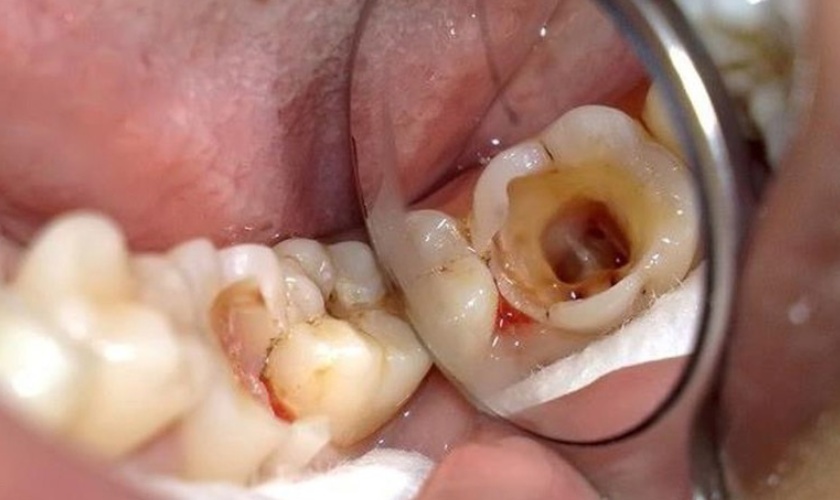

Răng đã điều trị tủy rất giòn và dễ vỡ

Răng đã điều trị tủy

Tủy răng bị viêm nhiễm gây đau nhức và có thể dẫn đến áp xe răng nếu không được điều trị. Lúc này, việc lấy tủy răng là rất cần thiết để giữ răng thật và ngăn ngừa những biến chứng đáng tiếc.

Tuy nhiên, răng đã điều trị tủy thường rất giòn và dễ vỡ theo thời gian. Cho nên, vấn đề răng hàm bị vỡ là điều sớm muộn có thể xảy ra.